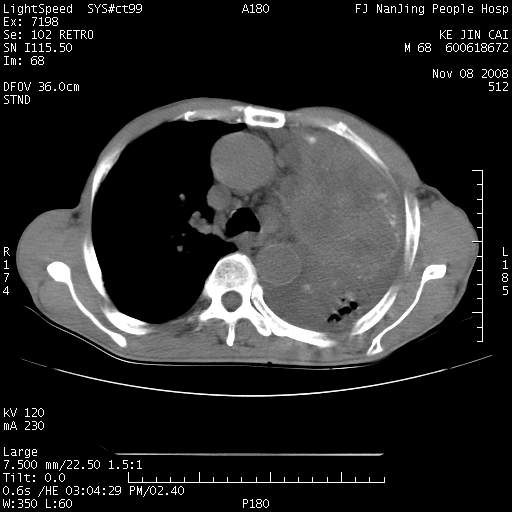

是个很有看头的病例,咋人气那么不旺?没多少人兴趣呢?这个病例几大怪:1   恶性肿瘤侵犯心肌左房怪,心肌一般不会被恶性肿瘤侵犯吧?2   左下肺均匀实变怪,内无含气,有别一般不张实变,含气肺泡完全为液体取代,而非一般不张实变的肺萎陷,冷不丁还以为是肿大的脾脏3   肿瘤本身怪,像tb肺不张4   这么有看头的病例没人气怪。呵呵。

追查病史,咳嗽,患者无发热,血象不高。据说2年前胸片检查怀疑肺ca曾行纤支镜检查,病理未见到癌细胞。无确切资料。

左肺恶性肿瘤侵犯肺动脉,左心房内瘤栓,胸膜转移。

左肺恶性肿瘤侵犯肺动脉,左心房内瘤栓,胸膜转移,少见,学习了。